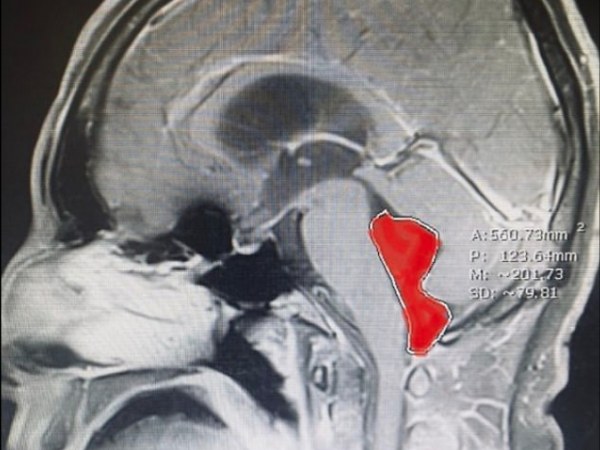

Мужчина из Техаса несколько месяцев мучился от головной боли, настолько сильной, что его рвало. Также он столкнулся и с внезапной потерей сознания. Обследование показало, что в его мозге имеется некое образование длиной около 4 см, однако тесты исключили опухоль. Дальнейшие анализы установили: в мозге мужчины находится свиной цепень. Врачи удалили его в ходе операции. Сейчас пациент полностью здоров.